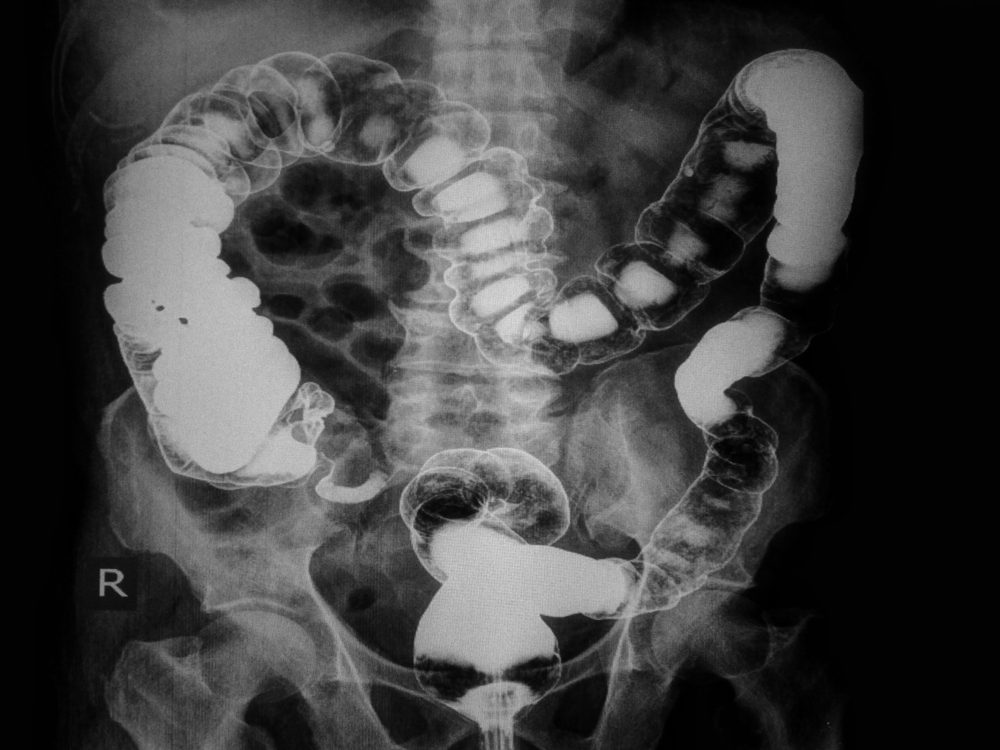

Diverticulitis

As you get older, your colon ages as well—and part of the aging process is the buildup of small, sac-like protrusions called diverticula. These are usually painless unless they become blocked or irritated. In this case, a localized infection known as diverticulitis can start (similar to appendicitis). Symptoms generally include a dull lower abdominal pain on the left side, and it can get progressively more severe over hours or a few days; you may be constipated, have a fever, and experience nausea and vomiting, explains Dr. Salsberry. “If diverticulitis is suspected, patients should seek prompt medical care, as, if left untreated, the infected diverticula can rupture, allowing the infection to spread into the abdomen or even the bloodstream,” he warns. “These complications can be life-threatening.” Here’s what GI docs wish you knew about diverticulitis.